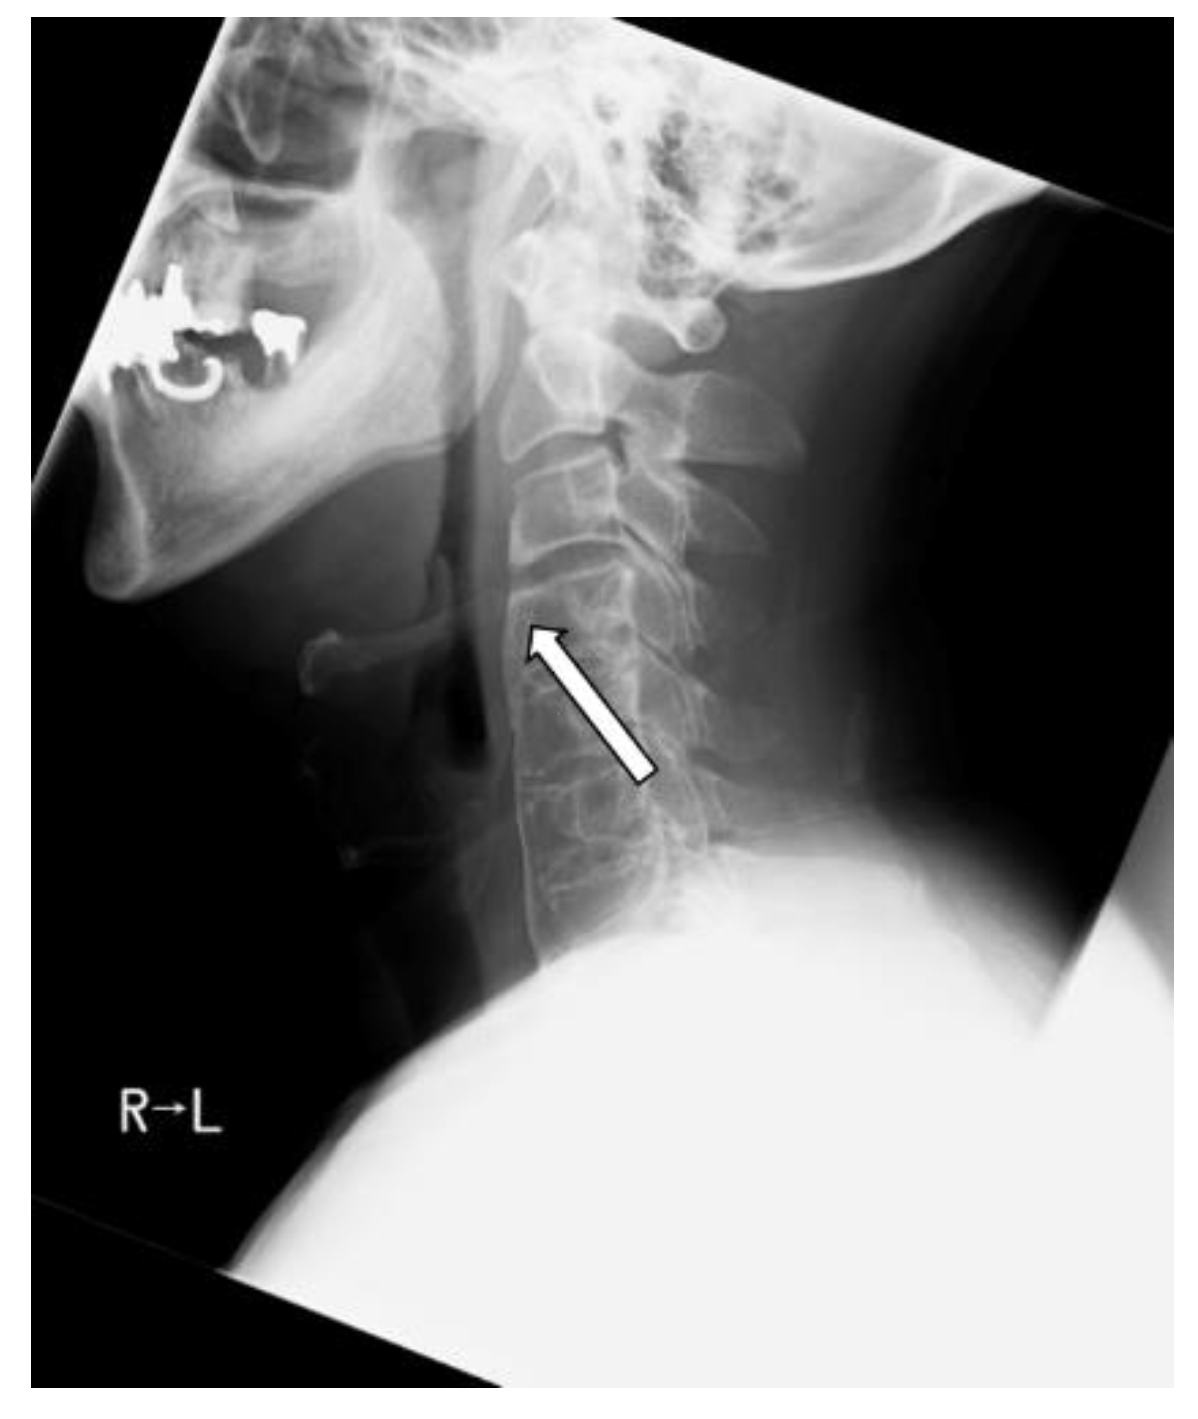

2.5. Clinical Presentations